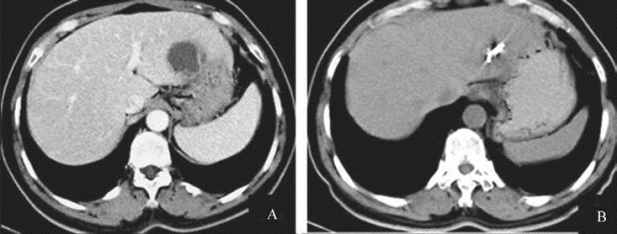

图21-36 肝囊肿经皮抽吸引流+硬化剂治疗

A.肝右叶囊肿;B.超声引导下经皮穿刺硬化治疗;C.术后半年复查囊肿完全消失